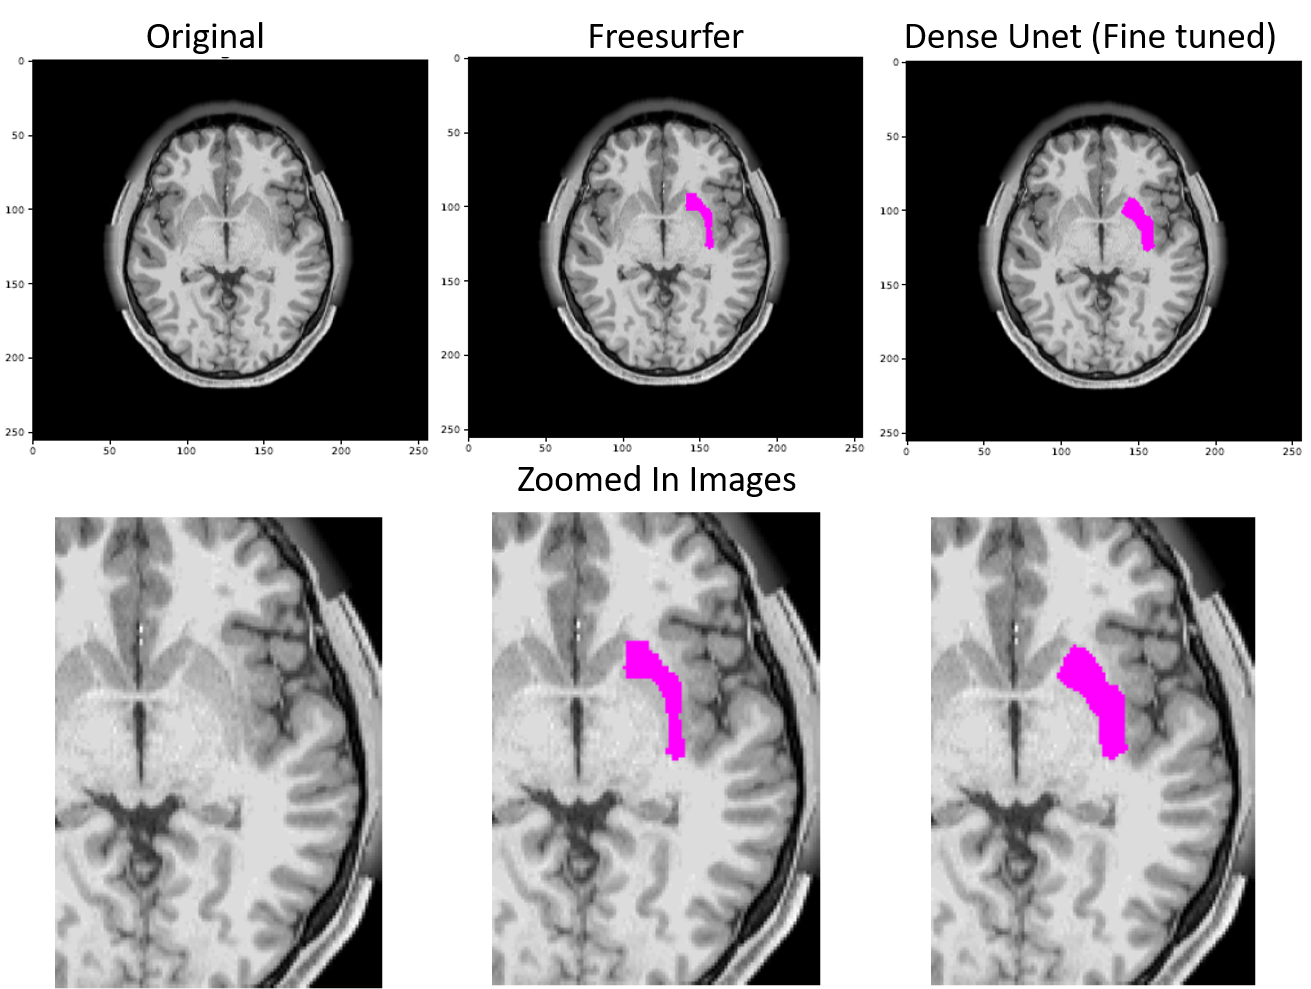

Figure 16 shows the difference in the segmentation outputs of Freesurfer and the proposed model.

Refer to caption

Figure 16: The image shows the original slice of an MRI, Freesurfer’s (FS’s) prediction for Putamen and the proposed model’s prediction of the same. It is evident that FS’s prediction don’t obey the boundaries and are non-natural looking grainy segmentation whereas the proposed model’s prediction obey the segment boundaries and are much more natural looking